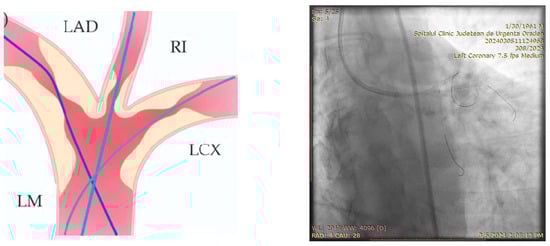

- Engage the left coronary artery with an EBU 4.0/8F guiding catheter. Wiring the three branches of the trifurcation (Floppy guide wires in LAD and RI, Hydrophilic guide wire in LCX) (Figure 14).